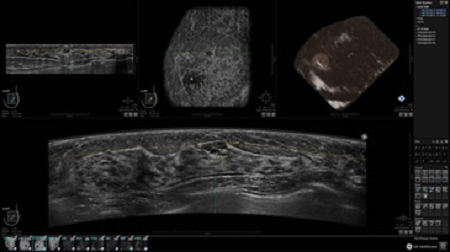

УЗИ-аппарат GE INVENIA ABUS позволяет проводить максимально операторонезависимые процедуры, что значительно снижает риск неправильной постановки диагноза и сопутствующие издержки на обработку информации. Система готовит отчет в течение 3-х минут после сканирования, это безусловное преимущество по сравнению с обычным УЗИ сканером.

• Получение объемных 3D изображений с возможностью покадрового просмотра

• Алгоритмы обработки изображений: алгоритм однородности изображения ткани (TEA), подавление зернистости, компенсация акустической тени от соска (NSC), определение границ молочной железы (BBD), определение стенки грудной клетки

• Отображение объемных 3D ультразвуковых изображений, которые состоят из традиционных поперечных и воссозданных коронарных и сагиттальных проекций

• Стандартизованная ориентация изображения: «толстый срез» в коронарной плоскости; поперечная; сагиттальная плоскость; радиальный и антирадиальный поворот изображения; просмотр исключительно области интереса

• Программное обеспечение Invenia ABUS Review Software для рабочей станции